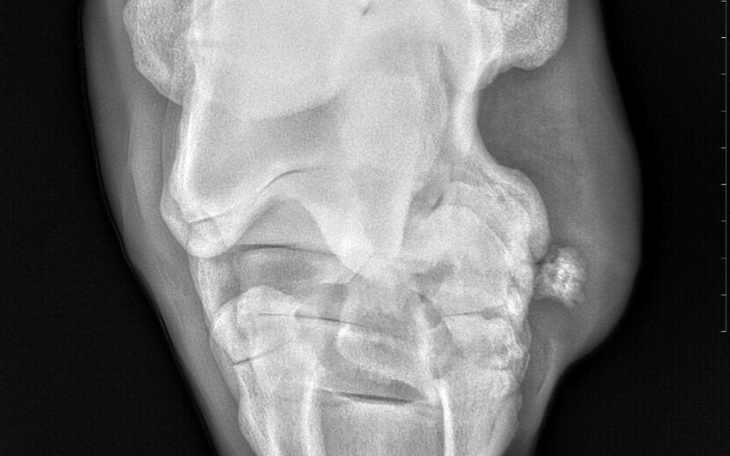

Witam pół roku temu kupiłem konia wszystko miało być super niestety jakiś czas temu koń zaczął kuleć i okazało się najgorzsze. Wyszedł szpat. Wszystkie plany związane z nim poszły na bok a mnie nie stać na leczenie. Potrzeba pieniędzy na ostrzykiwanie nogi i tabletki. Są to dla mnie duże koszty z racji tego że się jeszcze uczę przyda się każda złotówka nie pozwolę aby mój koń cierpiał